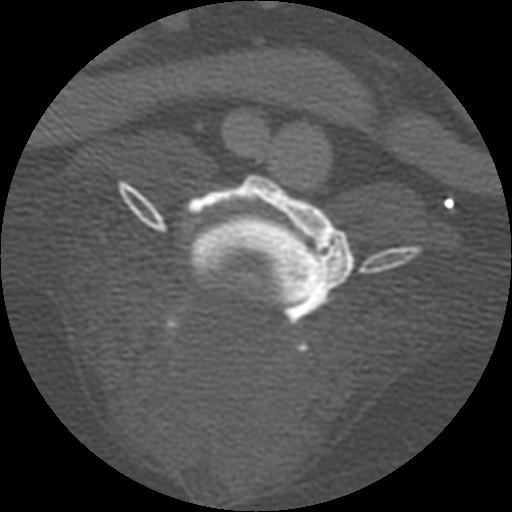

This week’s case is a 14-year-old female neutered Golden Retriever with progressive paresis of both hind limbs.

On the lateral radiograph, a large osteolytic site is present at the caudal aspect of the lamina of L4. This results in loss of the caudal half of the lamina and the articular facets of L4 with loss of the pedicles evident on the ventrodorsal projection. There is dural ossification in the cord. There is extensive ventral spondylosis throughout the lumbar vertebral column. No other sites of osteolysis are identified.

On the 1 mm, post contrast CT images, there is extensive osteolysis in L3 and L4 involving the vertebral bodies, laminae and dorsal spinous processes. There is a non contrast-enhancing soft tissue mass dorsal to the vertebrae.